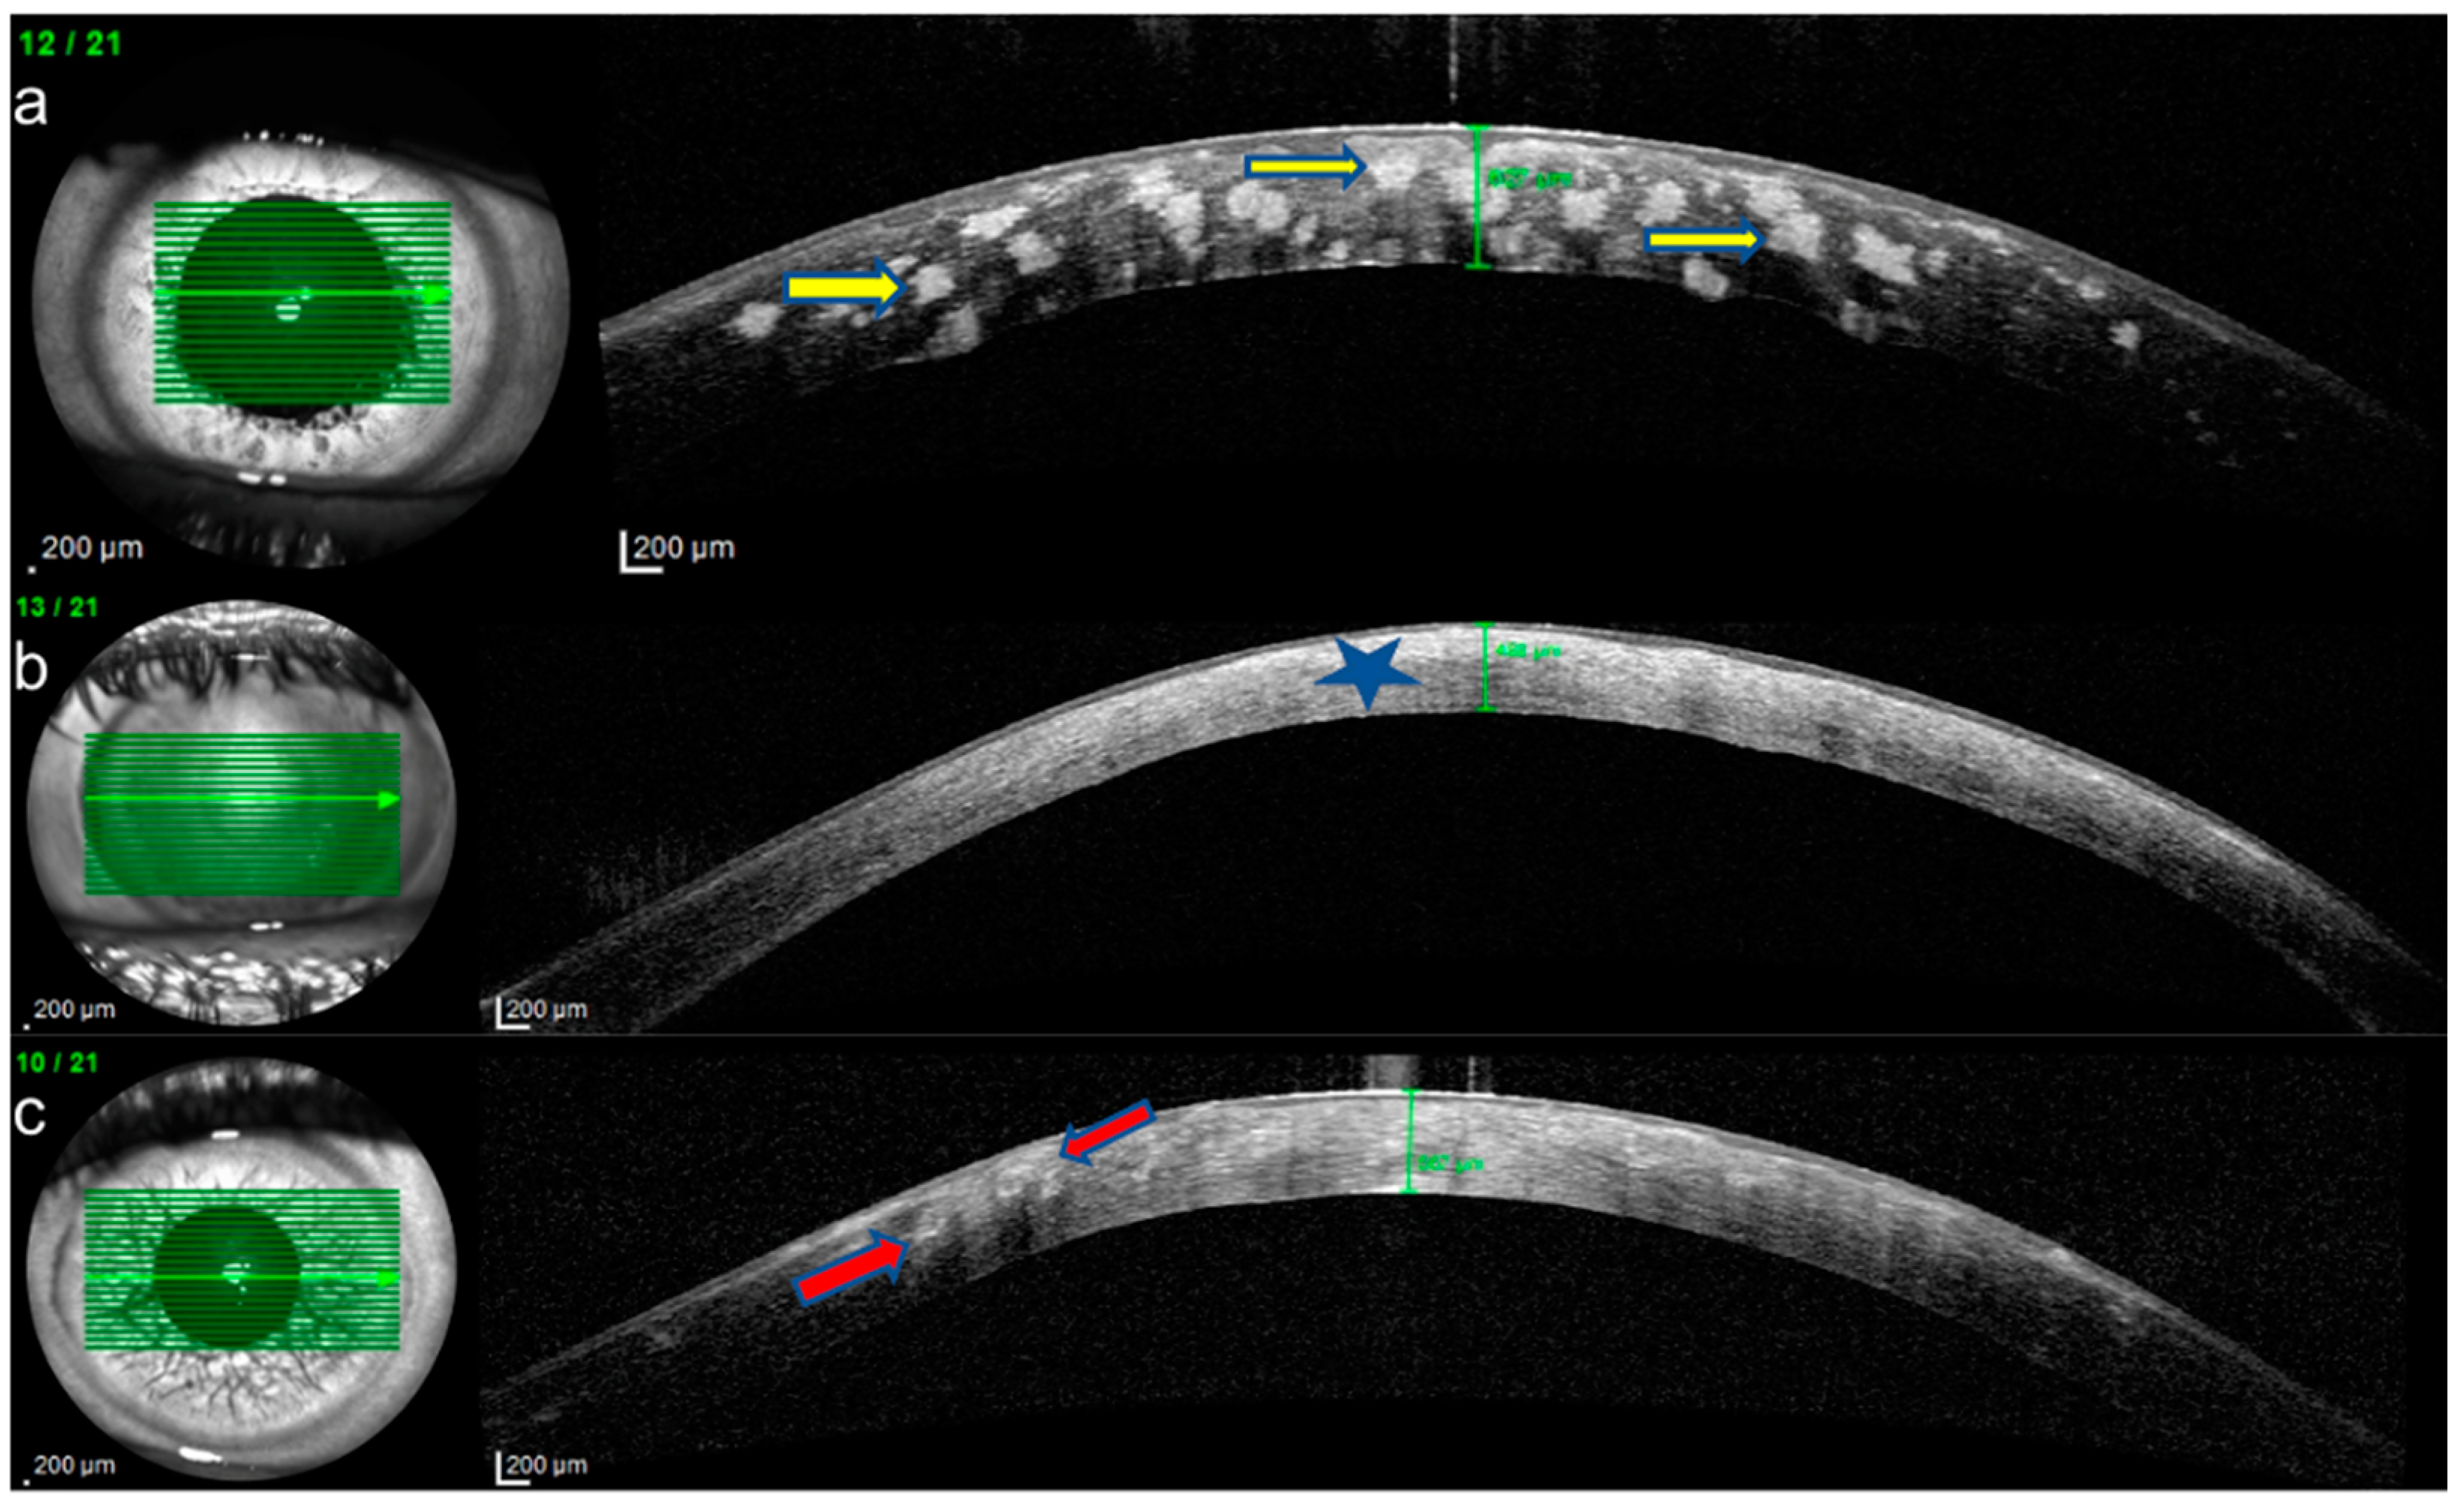

Figure 4.

Anterior segment optical coherence tomography (AS-OCT) imaging of corneal stromal dystrophies. (a) Granular corneal dystrophy (GCD): Highly reflective, discrete stromal deposits primarily located in the anterior and middle stromal layers, with extension to the posterior stroma and endothelium (yellow arrows). (b) Macular corneal dystrophy (MCD): Diffuse limbus to limbus increase in stromal reflectivity (blue star) extending from the Bowman to the endothelial layer and thinner corneal thickness (c) Lattice corneal dystrophy (LCD): Round and linear hyperreflective deposits (red arrows) observed predominantly in the anterior and middle stroma.

IVCM of eyes with GCD revealed round, highly reflective particles forming bigger, grapelike deposits throughout the stromal layer (Figure 2a). The deposit diameter was changing (20 µm–300 µm). A weak negative correlation was observed between age and depth (ρ = −0.165, p = 0.541). The stroma between the deposits remained relatively transparent, indicating areas of preserved tissue integrity (Figure 2a). Keratocytes appeared normal, with no signs of significant remodeling or cellular disruption. Epithelial involvement was observed in eight cases (66.66%) (Figure 3a), while the endothelial layer could not be visualized in nine patients. Two patients had recurrent erosions. In AS-OCT, highly reflective, discrete stromal deposits were observed mainly in the anterior and middle stromal layer, but also in the posterior stromal layer extending to the endothelium in some subjects (Figure 4a).

In MCD, IVCM revealed diffuse hyperreflective deposit accumulation throughout the whole stroma with characteristics dark striae inside (Figure 2b). The stromal sections showed a notable loss of keratocyte visibility, reflecting substantial stromal remodeling and disorganization. Epithelial involvement was observed in four cases (Figure 3b), while the endothelial layer could be visualized only in one patient. In some cases, round inflammatory cells and dendritiform cell clusters around the deposits and amorphous keratocytes were observed (Figure 5a,b). AS-OCT revealed a diffuse increase in stromal reflectivity extending from the Bowman to the endothelial layer and limbus to limbus (Figure 4b).

LCD exhibited distinct structural changes and epithelial disruption on IVCM. The hyperreflective deposits formed a branching, lattice-like pattern and were predominantly located in the stroma extending to the epithelium and, unlike MCD, the keratocytes were clearly visible between the deposits (Figure 2c). Epithelial disruption was a prominent feature, contributing to the recurrent epithelial erosions frequently associated with this dystrophy (Figure 3c). In patients with LCD, epithelial involvement was observed in 10 cases, while the endothelial layer could be visualized in 4 cases. Eleven eyes of six patients with LCD had recurrent corneal erosions. AS-OCT imaging supported these observations by demonstrating round and linear deposits mostly in the anterior and middle stroma. (Figure 4c).

The mean central corneal thickness (CCT) values for the three groups, excluding patients with prior corneal surgery, were as follows: 565.16 ± 49.62 µm for GCD (Figure 4a), 449.44 ± 65.45 µm for MCD (Figure 4b) and 569.91 ± 39.32 2 µm for LCD (Figure 4c). A one-way ANOVA test revealed a statistically significant difference in CCT among the three groups (p < 0.001). These findings indicate that MCD had a notably thinner corneal thickness compared to the other dystrophies.